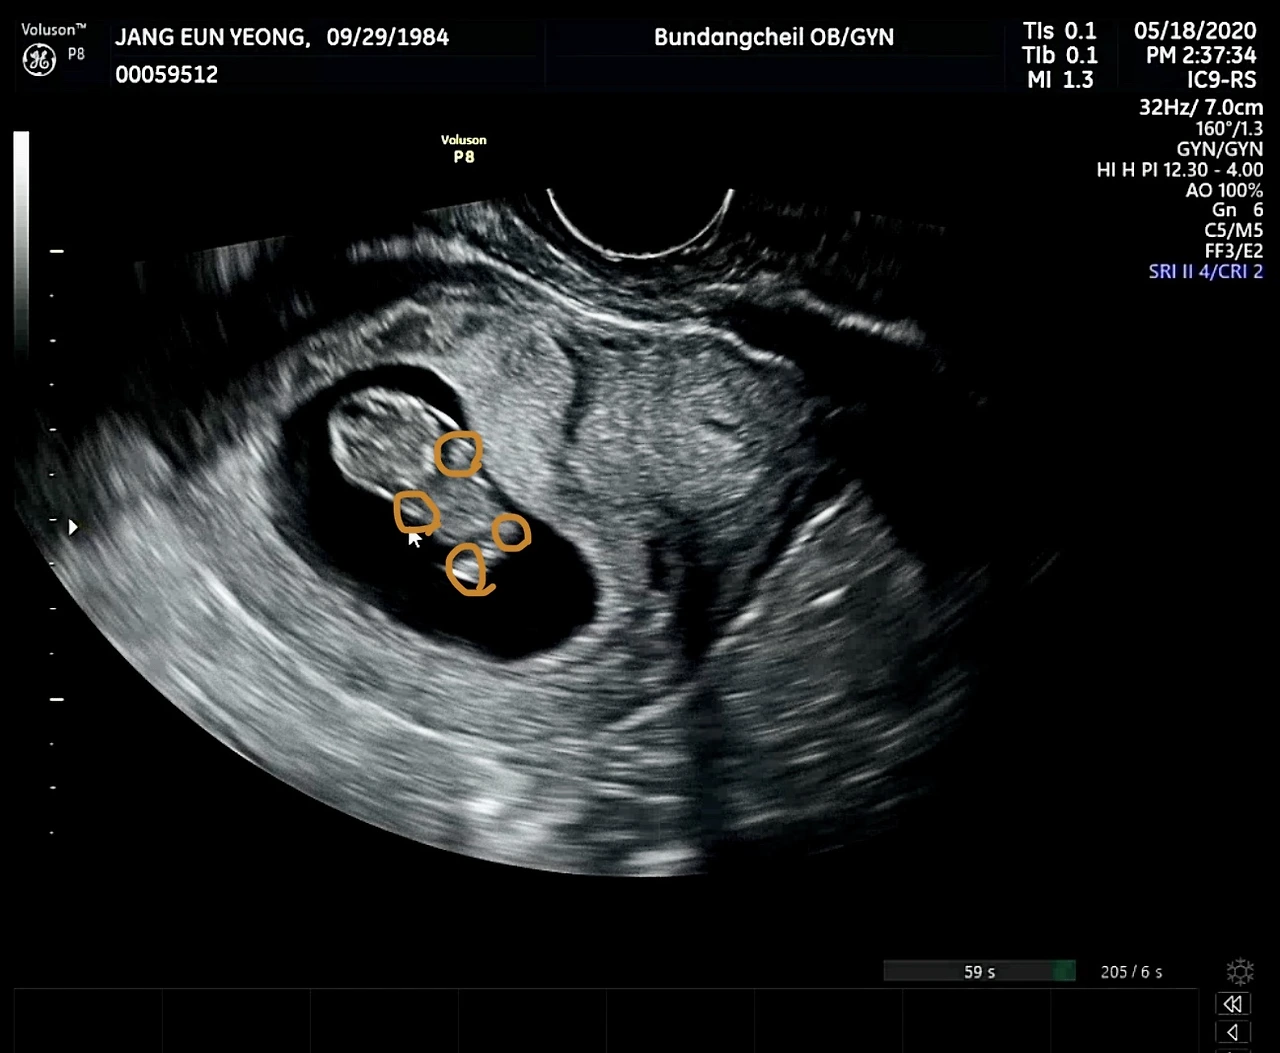

임신 사실을 확인하고, 2주 뒤에 찾아가 처음으로 심장소리를 들었을 때, 형체도 알아볼 수 없는 3미리 남짓의 작는세포의 우렁찬 울림을 기억한다.

그리고 또다시 2주 뒤,

너는 손, 발이라는 네 개의 꼭짓점으로 인사한다.

초음파를 같이 보던 남편은

“팔, 다리만 보이는거 보니까 딸인가봐요!!”

큰 웃음 선사.

그래 엄마도 잘 있어!!